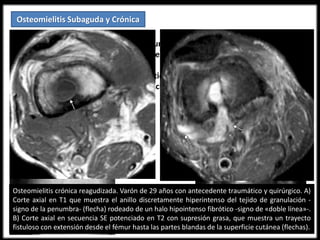

Osteomielitis crónica reagudizada. Varón de 29 años con antecedente traumático y quirúrgico. A)

Corte axial en T1 que muestra el anillo discretamente hiperintenso del tejido de granulación -

signo de la penumbra- (flecha) rodeado de un halo hipointenso fibrótico -signo de «doble línea»-.

B) Corte axial en secuencia SE potenciado en T2 con supresión grasa, que muestra un trayecto

fistuloso con extensión desde el fémur hasta las partes blandas de la superficie cutánea (flechas).